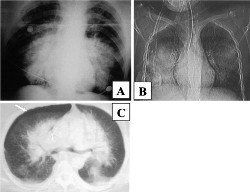

臨床表現和診斷:傷後有胸痛、胸悶、咳嗽、咯血等,嚴重者有明顯呼吸困難、發紺、咯血性泡沫痰等,還可用煩躁不安,肌抽搐等。胸部聽診可發現呼吸音減弱、濕性羅音、捻發音等。X線胸部攝片可有肺紋增強、點狀或片狀陰影等。超音波檢查可幫助診斷胸腔積液。此外用心電圖觀察心臟的改變。還可用肺動脈導管和血氣分析監測氣體交換障礙、肺內動靜脈分流增高等。